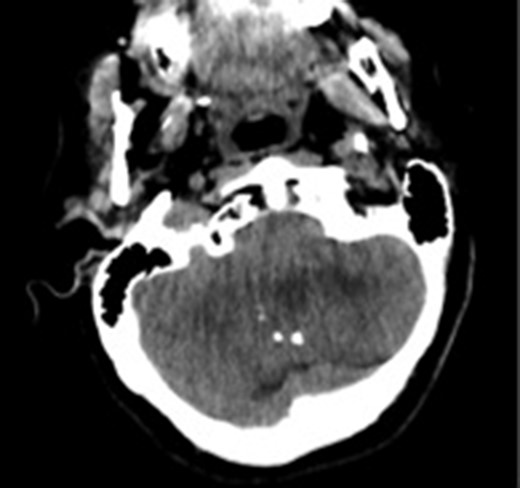

A 55-year-old woman presented with headache, dizziness and gait imbalance for 2 months. Patient’s history revealed a posterior fossa tumor that had been diagnosed 4 years ago prior to admission to our clinic. At that time, contrast enhanced of magnetic resonance imaging (MRI)showed the ill defined lesion, 5.5×3.5×4 cm in size without perilesional edema (Fig. 1A,B). During this 4 years period, her follow-up had been performed with serial MRI (Fig. 2A and B) and CT assessments (Fig. 3). Until 2 months ago, she had only intermittent headache. On neurological examination, she had cerebellar signs including ataxia and also bilateral papilledema through ocular investigations. CT assessment showed punctate calcified lesion demonstrated with undifferentiated margins of the lesion from the cerebellar parenchyma. The last MRI findings showed heterogeneous ill defined lesion without perilesional edema in vermis and extending to the adjoining cerebellar hemisphere at the supracerebellar infratentorial space with a dimension of 6.7×4×4 cm size causing compression of the fourth ventricle and marked hydrocephalous. The patient underwent surgery through a midline supracerebellar infratentorial approach in the prone position. It was a soft whitish intra-axial tumor, moderately vascular with a good plane between the vermis and cerebellum. A complete resection was achieved. The cerebrospinal fluid shunt was not decided to be placed (Fig. 4). Pathological diagnosis was reported as CLN. Immunohistochemical study, synaptophysin and neuron-specific enolase (NSE) immunopositivity were found (Fig. 5). In the mean time, glial fibrillary acidic protein (GFAP) was immunonegative and Ki-67 index was 2%. After operation, she had uneventful postoperative period and was discharged on seventh day.

Computed tomography image showing calcifications in the lesion. The margins of the lesion cannot be differentiated from cerebellar parenchyma.